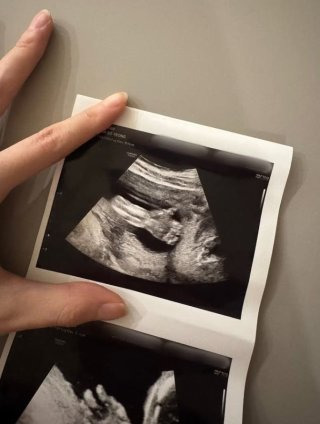

김소영 둘째 임신

김소영이 밝고 담담한 목소리로 둘째 임신 소식을 직접 전해 화제가 됐다. 김소영은 “또 한 명의 아기가 찾아왔다”고 전하며 6개월 차에 접어든 근황을 공개했다. 입덧으로 힘든 시간을 보냈지만 이제 안정기에 들어섰다고 말하며 “내년 봄, 수아의 동생을 만나게 될 것”이라고 기대감을 드러냈다.

유튜브 ‘띵그리TV’ 재개 역시 이 소식을 전하기 위한 선택이었다고 밝혔다. 지난해 유산의 아픔을 겪었던 부부가 새 생명을 맞이하게 되면서 많은 이들의 응원이 이어지고 있다.